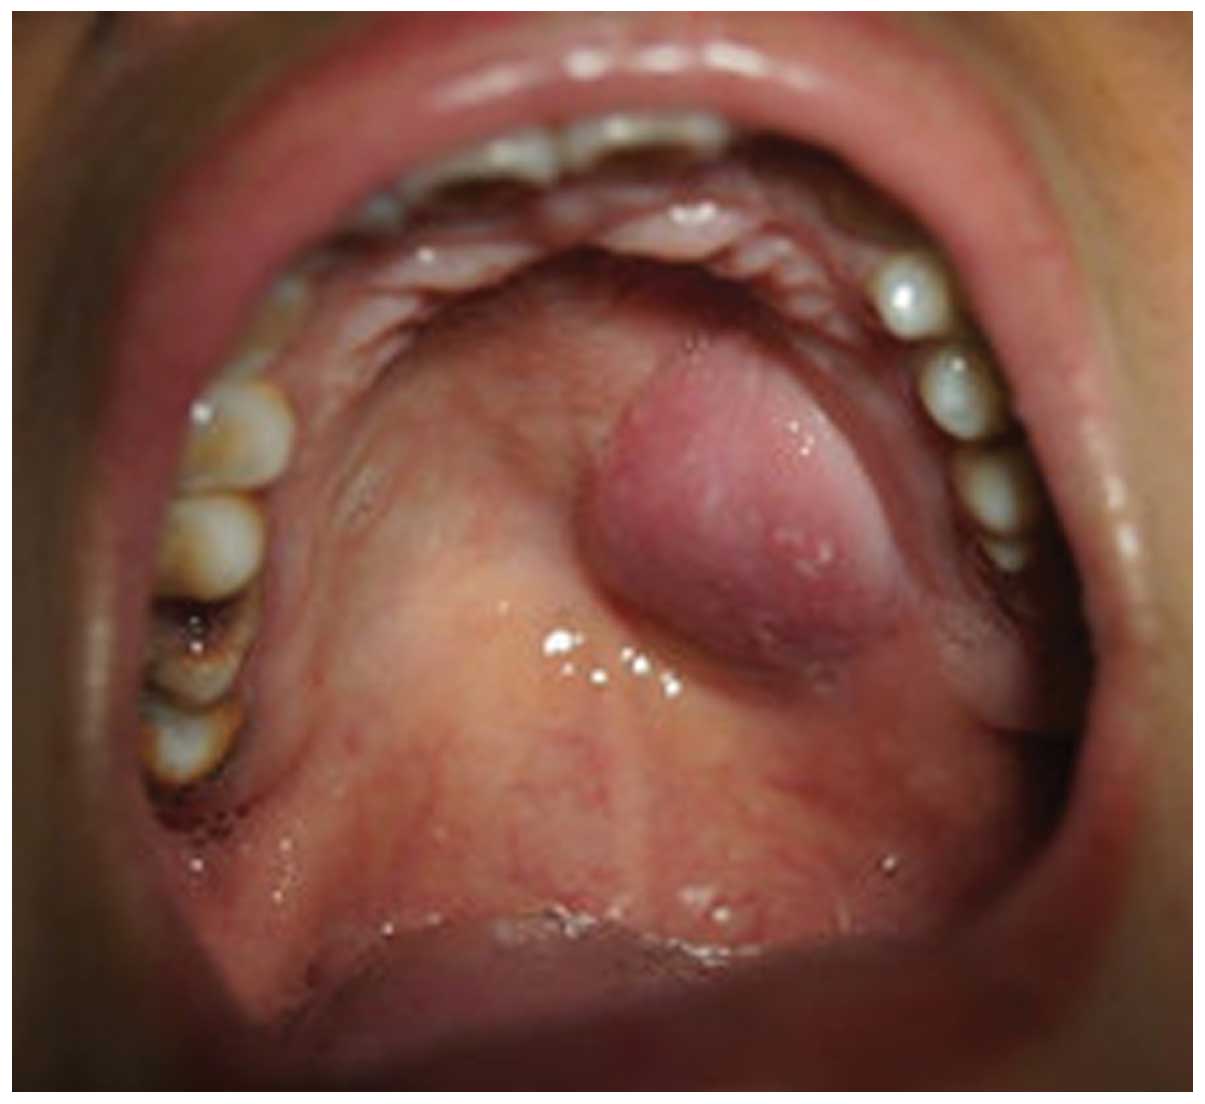

Figure 1

Intraoral image showing a nodular submucosal tumor on the left side of the hard palate.

A 38-year-old Chinese female was admitted to the Department of Stomatology at the Second Xiangya Hospital, of Central South University (Changsha, China) with a painless mass in her left palate. The patient stated that the mass was initially identified approximately one month previously. Intraoral examination revealed a well-defined, nodular mass in the left side of the hard palate (Fig. 1). The mass was non-tender and soft to palpation, with areas of fluctuance. The surface mucosa was red in color with no erosion, bleeding or ulceration. Magnetic resonance imaging delineated a mass lesion of 26 × 24 × 17 mm in size, located on the left hard palate with invasion into the nasal cavity (Fig. 2). The tumor exhibited isointensity on T1-weighted images and hyperintensity on T2-weighted images, with a moderately enhanced effect. No marked lymphadenopathy was identified according to imaging features and clinical examination. The patient was otherwise well, with no significant events in the medical history. An incisional biopsy was performed, which revealed irregular tumor nests of undifferentiated epithelial cells intimately intermingled with lymphocytes and plasma cells. The tumor cells exhibited a syncytial pattern with indistinct cell borders, vesicular nuclei, and large central nucleoli (Fig. 3). Immunohistochemically, the tumor cells were diffusely positive for cytokeratin AE1/AE3 (Fig. 4A). In situ hybridization for EBV-encoded RNA was diffusely positive in undifferentiated carcinoma, however, it was negative in the surrounding lymphoid stroma and adjacent salivary gland tissues (Fig. 4B). Endoscopy examination revealed a thickening of the nasopharynx. Multiple biopsies from the nasopharynx were subsequently performed, which were negative for tumor cells. A final diagnosis of primary LEC was determined. The patient underwent a partial maxillectomy without further surgical neck dissection. Adjuvant radiotherapy was suggested, however this was refused by the patient due to financial difficulties. The patient showed no evidence of remission during the postoperative follow-up of 12 months.